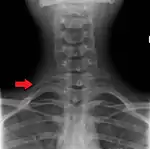

Variations in the number of ribs occur. About 1 in 200-500 people have an additional cervical rib, and there is a female predominance.[11] Intrathoracic supernumerary ribs are extremely rare.[12] The rib remnant of the 7th cervical vertebra on one or both sides is occasionally replaced by a free extra rib called a cervical rib, which can mechanically interfere with the nerves (brachial plexus) going to the arm.

X-ray image of a human chest, with ribs labelled.